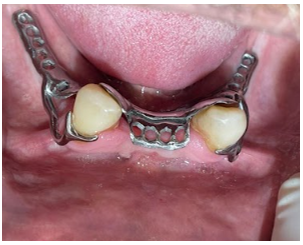

Figura 7: Os preparos para acomodação dos grampos de ação de ponta e MD inferior (33 e 43), foi realizado uma modificação no grampo MD para dar mais estabilidade para a PPR inferior, seguindo todas as características necessárias. A armação metálica foi provada em boca. Observou-se passividade e adequada ação retentiva dos grampos.